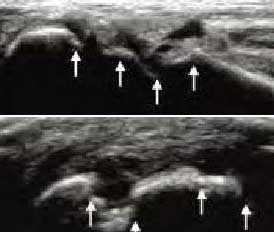

4、具备软组织超高分辨率 区分关节受损层级

肌骨超声通过平面成像能力发现RA关节软骨微小病变,早期就能准确反映出软骨下骨质线回声增高程度,关节软骨表面是否毛糙模糊凹凸不平、形态是否规则、有无明显隆起或缺损形成,判断早期RA软组织改变及RA骨质受损状况。

Ⅰ级

骨表面欠平整骨关节面边缘不整齐、模糊,形成不规则间隙

Ⅱ级

骨质中断或缺失骨表面出现弧形条状低回声,软骨表面不规则变薄、缺损形成

Ⅲ级

骨表面凹凸不平骨表面缺损融合成广泛的骨质破坏、侵蚀